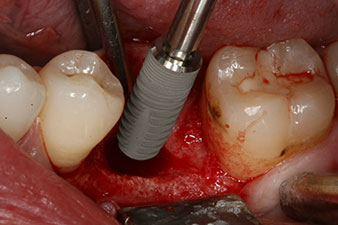

El torque en el momento de la carga mecánica fue de 43 Ncm. Asimismo, después de atornillar un poste de medición especial adaptado al sistema de implante (SmartPeg), el valor ISQ se determinó con la sonda del módulo Osstell ISQ de W&H.

Este módulo Osstell ISQ que se encuentra disponible como accesorio para la unidad Implantmed de W&H y se acopla al motor de implantes (véase figura 11). El valor ISQ adimensional fue de 64 justo en el momento de la inserción en la dirección bucovestibular y de 68 en la dirección mesiodistal (valor máximo = 100).

Este habría permitido una cicatrización abierta o incluso un tratamiento inmediato. Sin embargo, como no se disponía de suficiente hueso en la parte crestal del implante, el área se aumentó con las virutas óseas recopiladas durante la preparación del lecho del implante y se suturó para que no penetrara saliva.